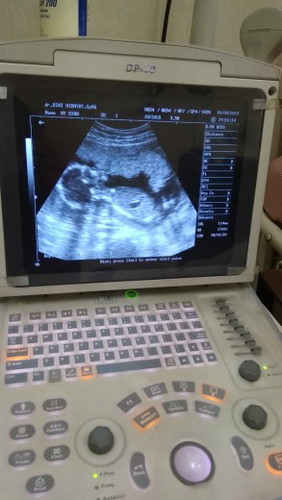

bun bun~ 17wk trnyata dan blm keliatan jk-nya kata dokter. ohya bun, di uk brapa disuruh tes lab dll? saya kok blm disuruh aja sama obgyn-nya~

Saya 15week udah keliatan. Tapi masih prediksi awal bun. Kan kita gatau perkembangan janin nantinya gimana. Dan tergantung sama posisi janin saat di USG. ngumpetin jknya apa pas nampangin. Saya belum tes lab dr dokter obgyn. Kalau dr bidan saya dapat tes darah, meliputi goldar, HB, & HIV. Saya sudah bertanya sama dokter, kapan waktunya tes lab. Nanti tunggu instruksi kata dokter obygn saya bun. Masing-masing dokter punya pengobatan dan saran sendiri. Makanya banyak bumil ganti2 dokter/bidan karena kurang sreg dengan pelayanannya. Tergantung bunda mau gimana

Baca lagiBiasanya posisi dede nya nutupin bun, kmarin aku uk 15week blm klihatan, pas 20week dlihat lg ktana jg blm klihatan soalnya dede kakinya nutupin tapi ditunggi dulu aga lama dede nya kan gerak2 bun, nah akhirnya kelihatan juga jk nya heehe, aku cek lab pas uk 11week bun. Katanya selama kehamilan min 2x cek lab pas tm1 sm tm3.

Baca lagiaku kmren usg 18 week blm bisa klihatan bun..soalnya posisi dede nya g mendukung alias pas melintang..udah di tungguin di goyang2 sm dokter ttp blm mau..trus dsrh balik lg bln dpn..klo cek lab aku di usia 13 week kmren..

Saya kemarin 17week keliatan bun, cuma saya belum yakin jd nunggu usg minggu depan lagi, biasanya 2x usg sama biasanya fix.. Harusnya tes lab tm1 sama tm3 bun, cuma saya kemarin baru disuruh pas tm2

Sy kmr d usia 16w dah keliatan JK nya bun.. Tp balik lagi tergantung posisi janinnya, mgkn malu jadi d umpetin, hihihi.. Sy kmr cek lab d TM1 & skr d TM3 d suruh cek lab lagi ama dokternya